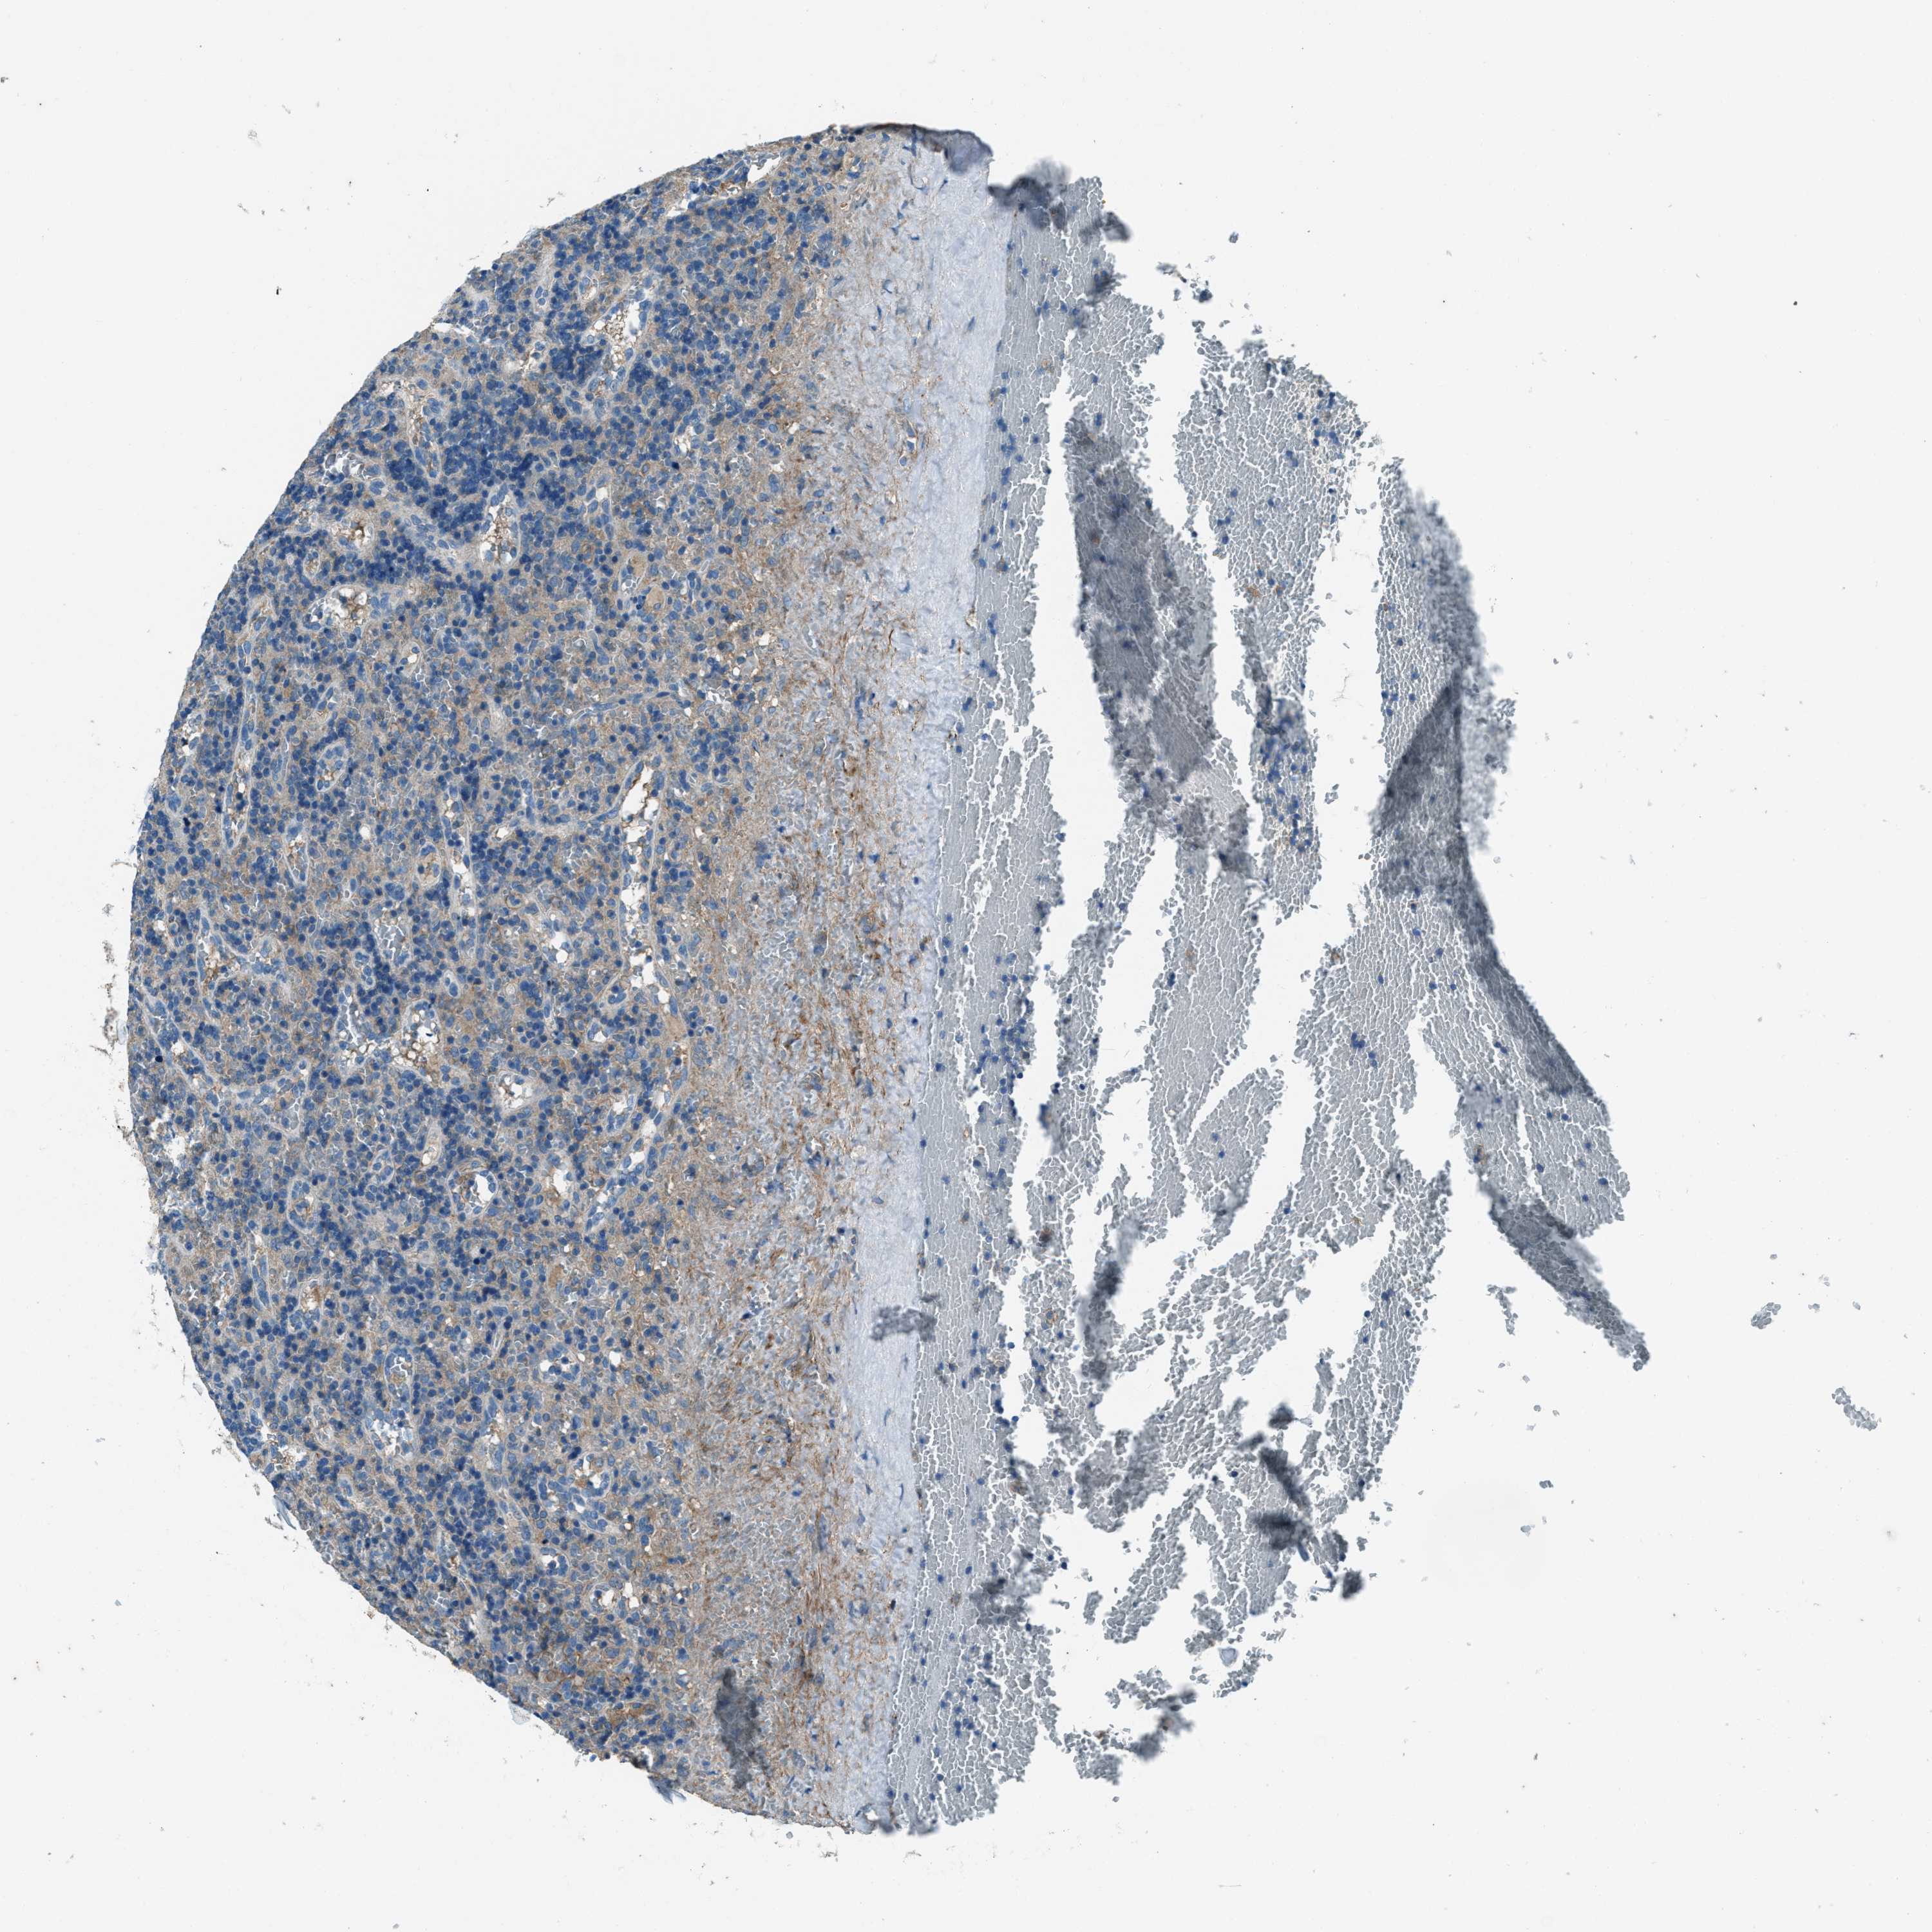

LYMPHOMA - Protein expressioni

A mouse-over function shows sample information and annotation data. Click on an image to view it in a full screen mode. Samples can be filtered based on level of antibody staining by selecting one or several of the following categories: high, medium, low and not detected. The assay and annotation is described here.

Antibody stainingi

Antibody staining in the annotated cell types in the current human tissue is reported as not detected, low, medium, or high, based on conventional immunohistochemistry profiling in selected tissues. This score is based on the combination of the staining intensity and fraction of stained cells.

Each image is clickable and will lead to virtual microscopy that enables deeper exploration of all samples and also displays staining intensity scores, fraction scores and subcellular localization as well as patient and tissue information for each sample.

Antibody HPA020095

Antibody HPA020138

Antibody CAB010878

Antibody CAB080402

Staining

High

Medium

Low

Not detected

Intensity

Strong

Moderate

Weak

Negative

Quantity

>75%

75%-25%

<25%

None

Location

Nuclear

Cytoplasmic/membranous

Cytoplasmic/membranous,nuclear

Hodgkin's disease, NOS

Malignant lymphoma, non-Hodgkin's type, High grade

Malignant lymphoma, non-Hodgkin's type, Low grade